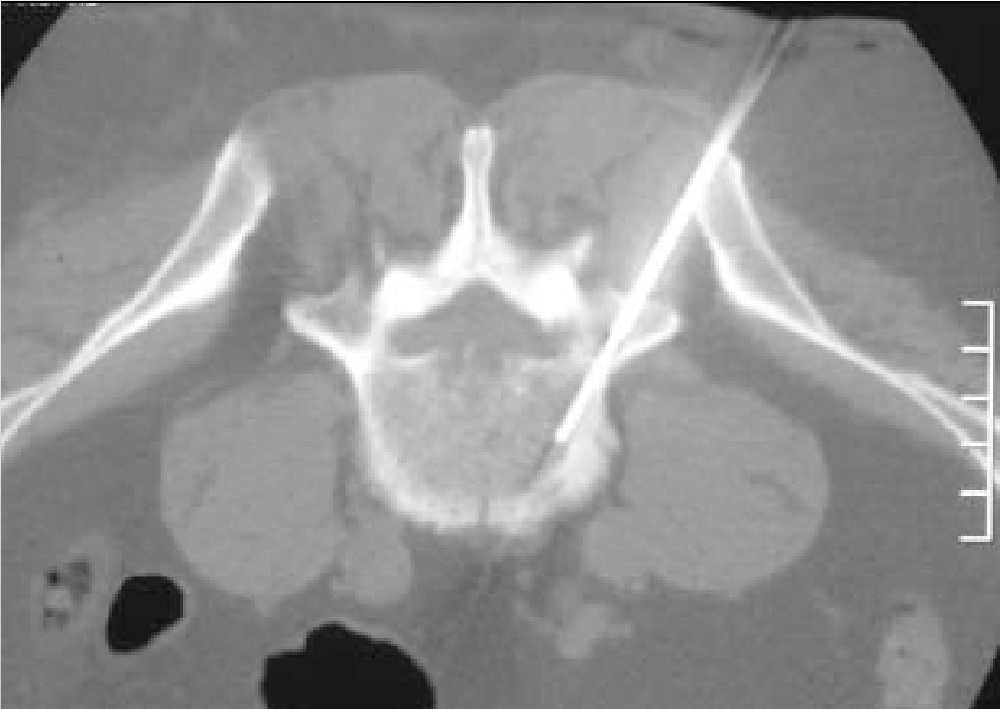

The hospital called and the date was set for the biopsy. This type of biopsy is nothing like what I had prior. You’re awake for it. It has to be done by a specialist with an Oncologist present. The entry area is within mm of the spin and the least mistake or simple error could result in paralysis. The procedure was performed without anesthetic. I had to stay perfectly still for the entire procedure. It was slightly painful but really more like bad pinches to the back. The radiologist was the same doctor that had preformed the ultrasound back in Feb 2014 when I was first diagnosed. He was extremely cautious. The needles were guided by a CT Scan, so as he placed each needle into position he had to leave the room and watch the CT Scanner. It felt like hours but in reality the entire procedure from start to finish took about 30 minutes . It is preformed in a radiology unit, basically the CT Scanner is used to guide needles into the lymphoma site it is quiet grueling. They managed to get 12 samples.